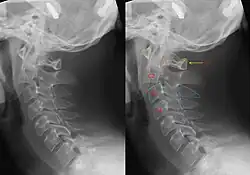

Fratura do enforcado

Fratura do enforcado ou fratura do pendurado é o nome coloquial dado a uma fratura de ambos os pedículos, ou partes interarticulares, do áxis (Vértebra Cervical 2).[1]